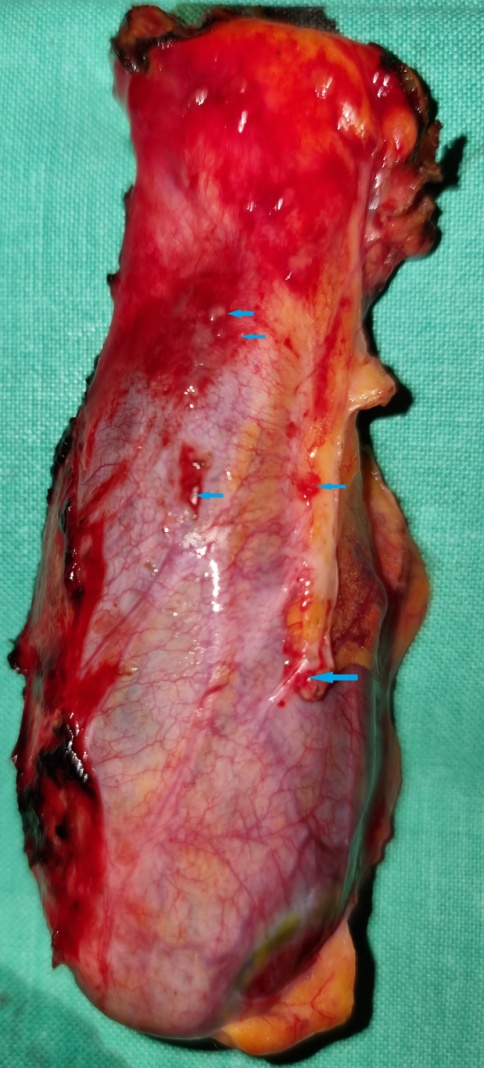

Εκταμέν παρασκεύασμα που εμφανίζει πενταπλά σύγχρονα αδενοκαρκινώματα ορθού (A, B, C, D)